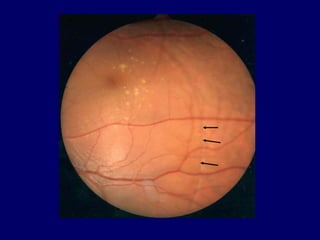

Congenital pit is an atypical coloboma usually located

on the temporal edge of the disc, associated with irregular

defects in the juxtapapillary choroid and pigment

epithelium. Macular fibers passing through this area

often are affected and corresponding changes in the

retinal ganglion cell layer and in the visual field occur.

 When the pit is located temporally on the edge of the disc it

may become associated with abnormalities in the macula

 In the vast majority of cases there is only one pit and is

unilateral , varying in size between 150 to 500 m in diam.